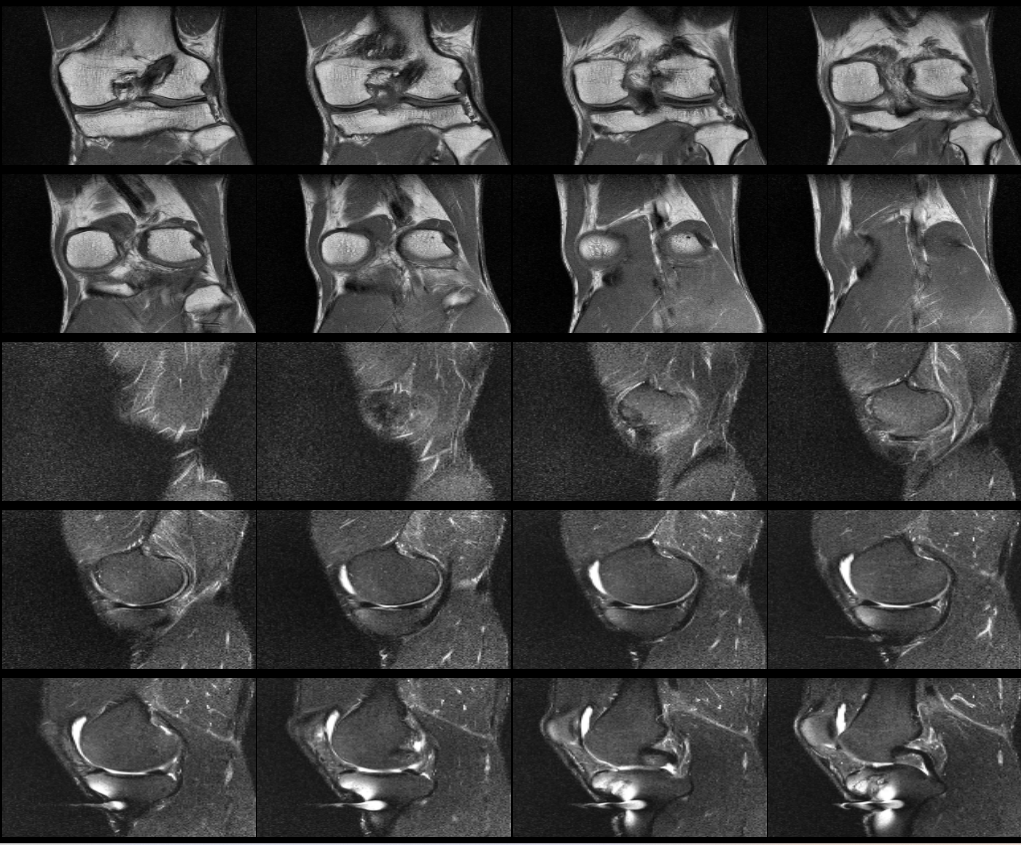

무릎 십자인대 재건술 후 약8년이 지난 지금 mri를 찍었습니다. 판독부탁드립니다ㅠㅠ

약 8년전 무릎 전방십자인대 재건술을 했는데 , 운동관련 직종이다 보니 , 운동을 많이 합니다.

최근들어 무릎에 불편한 통증이 있어 mri를 찍었는데 ,

활막염이라는 말만 들었는데 , 여러 선생님들의 의견을 듣고 싶어 사진올립니다. 판독해주시면 정말 너무너무

안녕하세요. 채홍석 의사입니다. MRI 퀄리티가 나빠서 판독은 어렵겠네요.